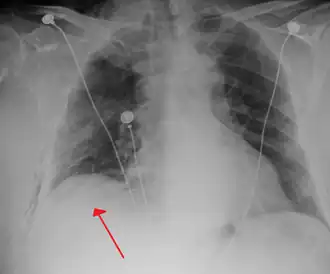

Chest X-ray

A plain chest radiograph, ideally with the X-ray beams being projected from the back (posteroanterior, or "PA"), and during maximal inspiration (holding one's breath), is the most appropriate first investigation.[35] It is not believed that routinely taking images during expiration would confer any benefit.[36] Still, they may be useful in the detection of a pneumothorax when clinical suspicion is high but yet an inspiratory radiograph appears normal.[37] Also, if the PA X-ray does not show a pneumothorax but there is a strong suspicion of one, lateral X-rays (with beams projecting from the side) may be performed, but this is not routine practice.[18][22]

Chest X-ray showing a pneumothorax on the right (left in the image), where the absence of lung markings indicates that there is free air inside the chest -

Chest X-ray showing the features of pneumothorax on the left side of the person (right in image)

It is not unusual for the mediastinum (the structure between the lungs that contains the heart, great blood vessels, and large airways) to be shifted away from the affected lung due to the pressure differences. This is not equivalent to a tension pneumothorax, which is determined mainly by the constellation of symptoms, hypoxia, and shock.[16]

The size of the pneumothorax (i.e. the volume of air in the pleural space) can be determined with a reasonable degree of accuracy by measuring the distance between the chest wall and the lung. This is relevant to treatment, as smaller pneumothoraces may be managed differently. An air rim of 2 cm means that the pneumothorax occupies about 50% of the hemithorax.[18] British professional guidelines have traditionally stated that the measurement should be performed at the level of the hilum (where blood vessels and airways enter the lung) with 2 cm as the cutoff,[18] while American guidelines state that the measurement should be done at the apex (top) of the lung with 3 cm differentiating between a "small" and a "large" pneumothorax.[38] The latter method may overestimate the size of a pneumothorax if it is located mainly at the apex, which is a common occurrence.[18] The various methods correlate poorly but are the best easily available ways of estimating pneumothorax size.[18][22] CT scanning (see below) can provide a more accurate determination of the size of the pneumothorax, but its routine use in this setting is not recommended.[38]

Not all pneumothoraces are uniform; some only form a pocket of air in a particular place in the chest.[18] Small amounts of fluid may be noted on the chest X-ray (hydropneumothorax); this may be blood (hemopneumothorax).[16] In some cases, the only significant abnormality may be the "deep sulcus sign", in which the normally small space between the chest wall and the diaphragm appears enlarged due to the abnormal presence of fluid.[19]